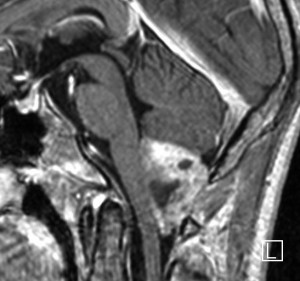

第4脳室床に発生した典型的な上衣腫 EPN-PFA の画像です。水頭症になって,頭痛と嘔吐,意識障害で発症しました。典型的なMRI画像と病理所見です。MRIでは第4脳室からマジャンディー孔を越えて脊髄背側まで長く腫瘍が伸びています。腫瘍内部に小さなのう胞が複数みられます。病理像では,血管周囲に細胞核がない無核野が認められます。血管周囲に伸びた繊細な単極性突起が集まった領域です。これは,血管周囲偽ロゼット perivascular pseudorosette という上衣腫に特徴的な病理所見です。

幼児の巨大な上衣腫です。左ルシュカ孔から延髄を取り囲む様に小脳延髄角槽に進展しています。最も典型的で治療が難しいタイプです。これはT2強調画像ですが,ガドリニウム増強されないものでした。

左が術前,右が術後です。脳底動脈の周囲が摘出できませんでした。幼児ですが手術後には局所照射をするしか方法がありません。